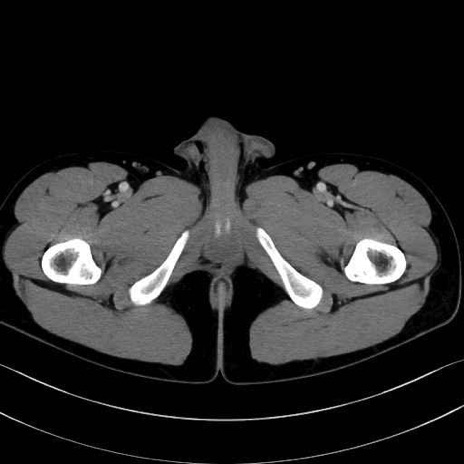

4. 深層外旋六筋(股関節の深部)

梨状筋 (Piriformis)

内閉鎖筋 (Obturator internus)

外閉鎖筋 (Obturator externus)

大腿方形筋 (Quadratus femoris)